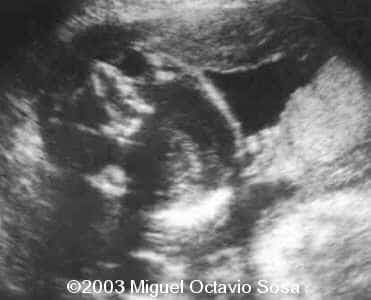

19-year-old primigravida. During third week of pregnancy, she is vaccinated with anti-measles vaccine, without knowing about the pregnancy. There are no important details before the pregnancy. These are images of the face of the fetus. Pay specific attention to the midface.

19-year-old primigravida. During third week of pregnancy, she is vaccinated with anti-measles vaccine, without knowing about the pregnancy. There are no important details before the pregnancy. At 22nd week, an ultrasound is performed demonstrating a single nasal channel on the left side and absence of right nostril.